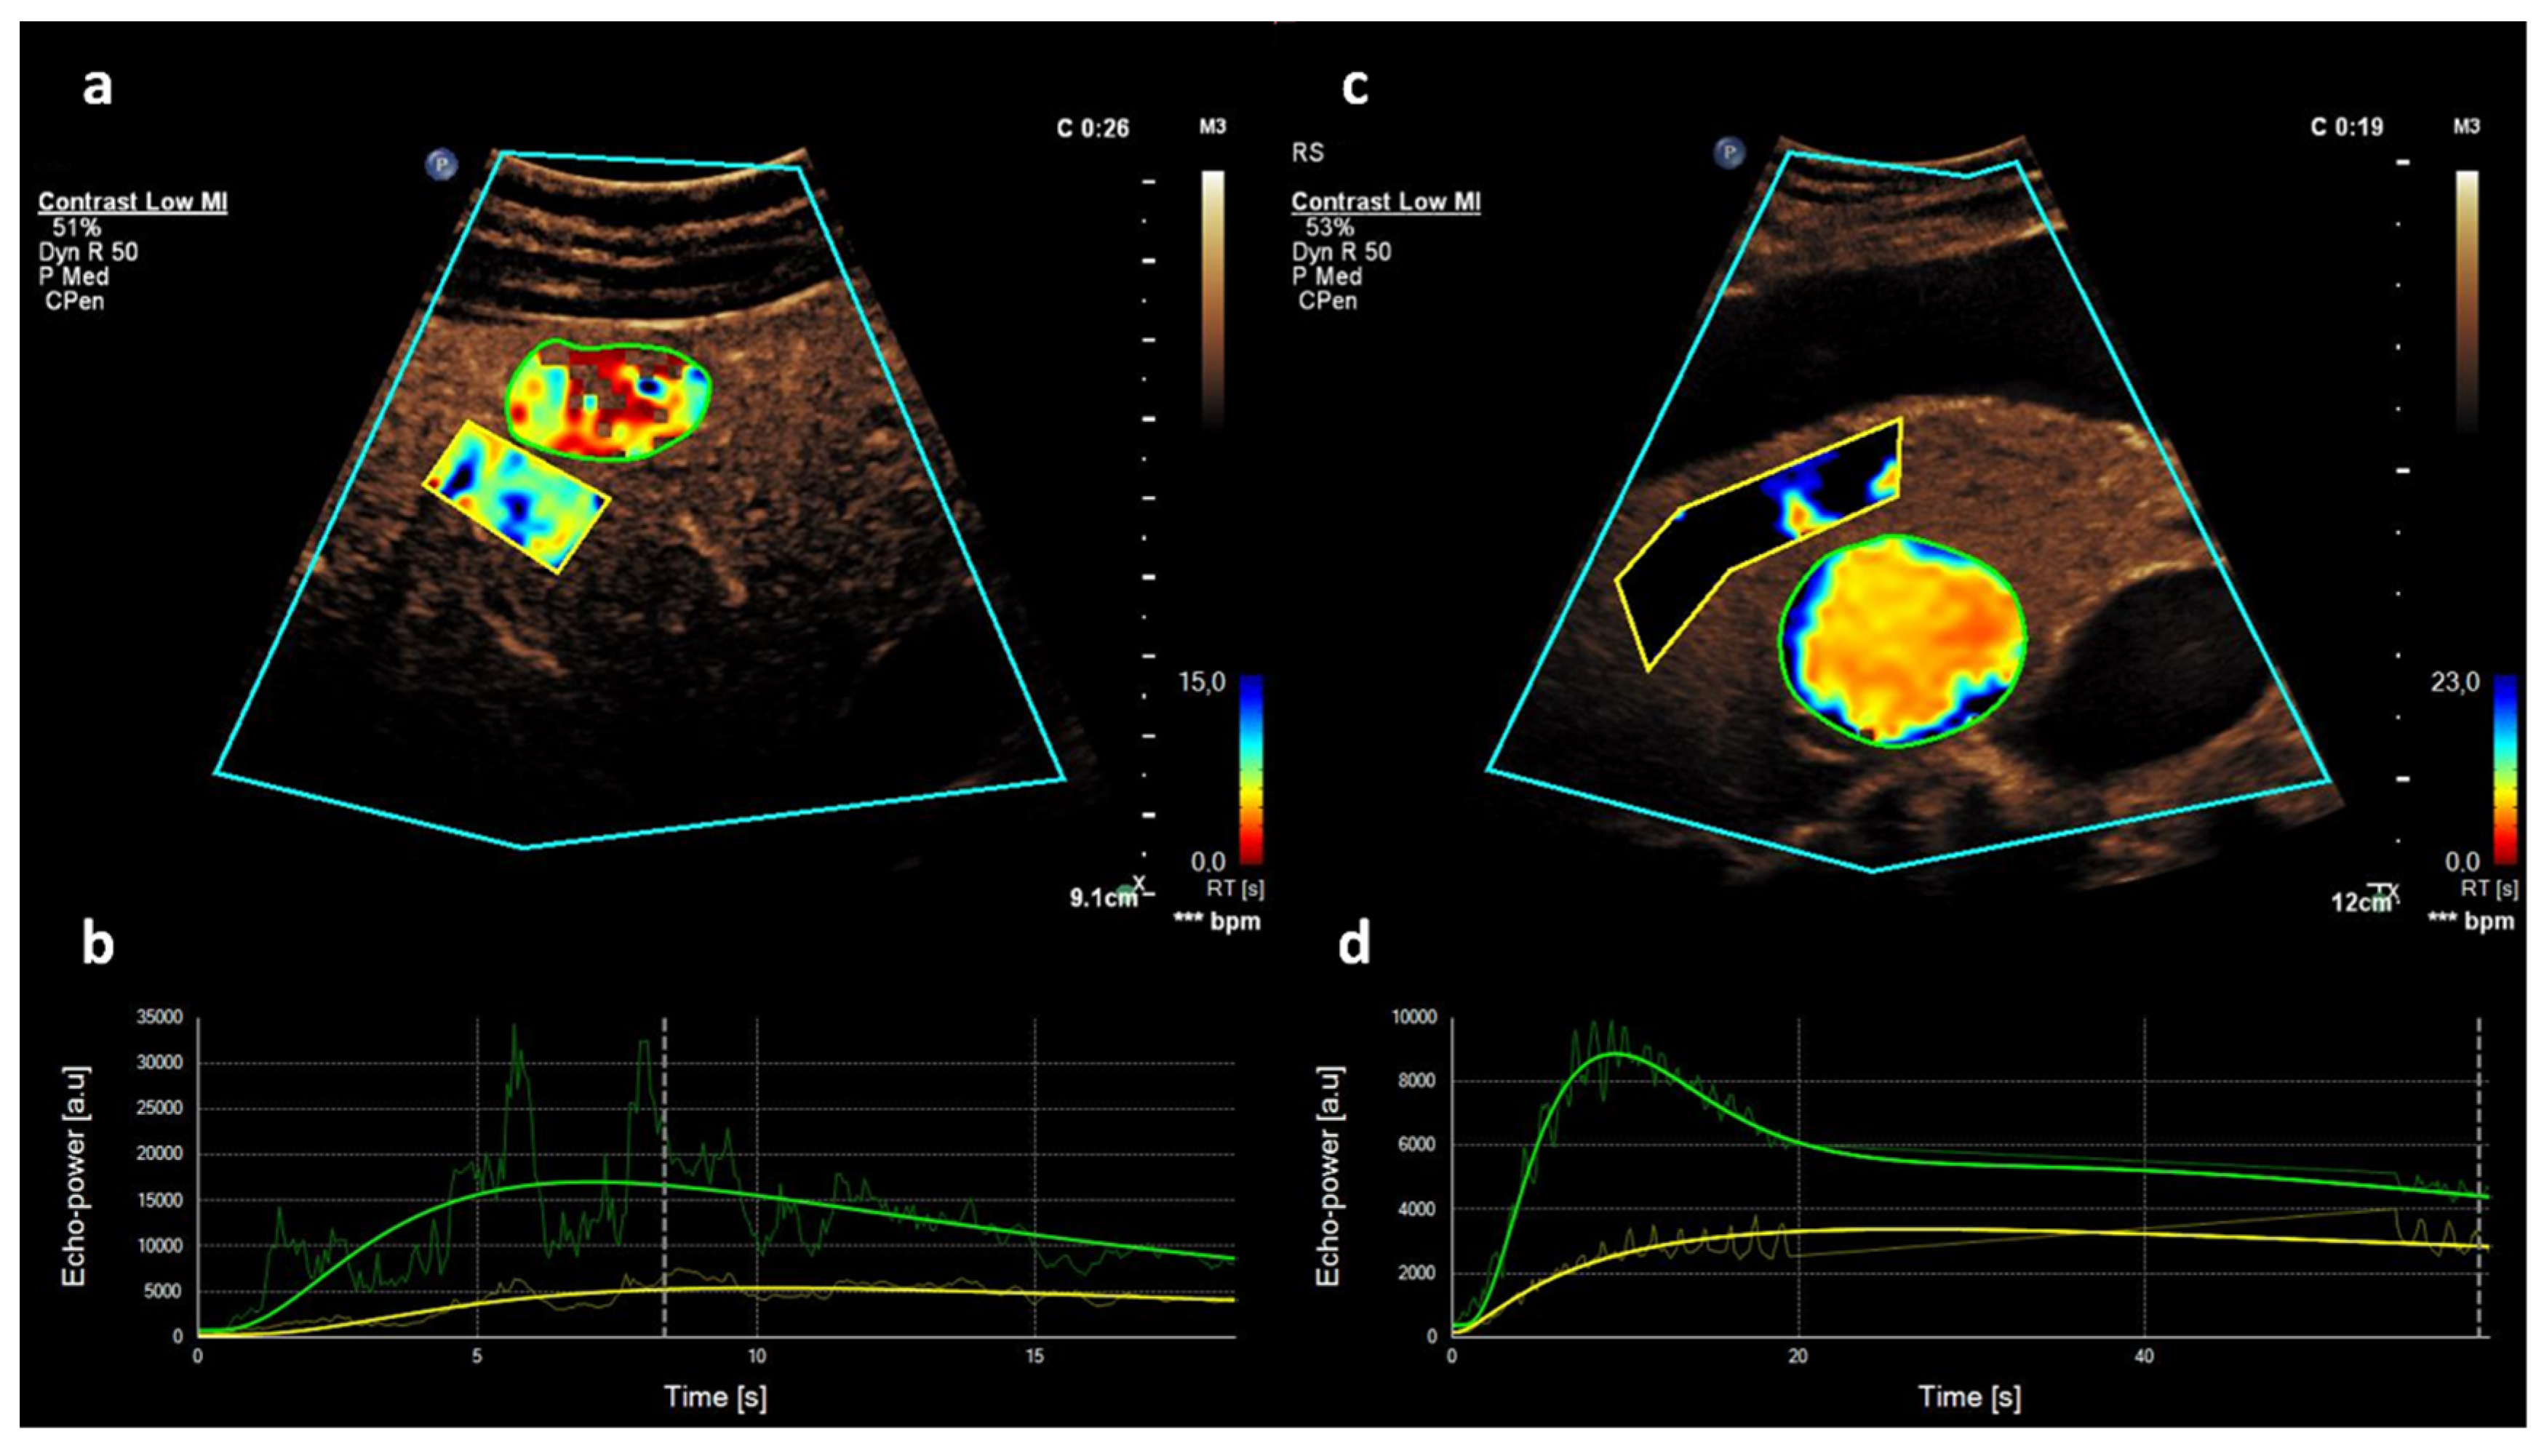

2.2. CEUS

2.3. Quantitative CEUS Assessment